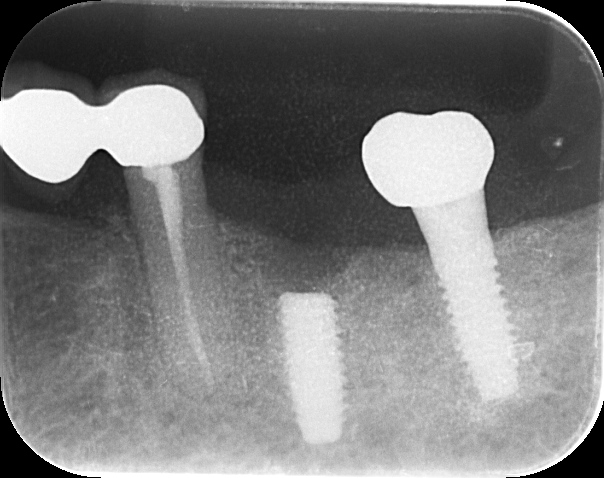

治療前

インプラント体にアバットメント(土台)装着

-

ジルコニア修復